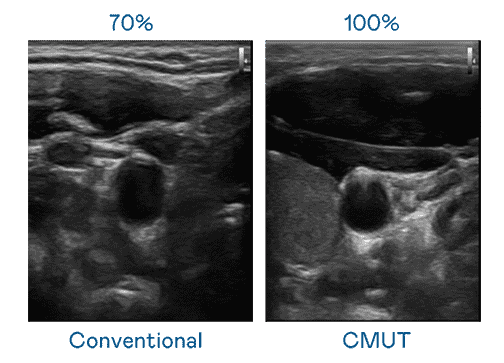

CMUT 技术是一种用电容式微机电元件来产生超音波讯号的技术。。。。与传统 PZT 压电式技术相比,,CMUT 频宽增加 30%,,更宽频的超音波讯号让影像解析度大幅提升,,,,是实现高影像品质医疗超音波扫描、、、促进精准医疗发展的关键技术。。。。

大频宽带来超清晰影像

超音波影像的解析度高低,,,,首先取决于探头能发出的讯号频宽。。。。尊龙集团 CMUT 可提供高清晰的超音波讯号,,,,提供高频宽、、高灵敏度、、影像纹理细节更高的超音波影像,,协助医护人员缩短影像判读时间及利用精准的医疗影像进行诊断。。